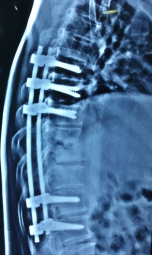

In some patients with deformity in spine or those with spinal cord compression causing paralysis, surgery to stabilise the spine and decompress the spinal cord/nerves is required. Surgical treatment in right time can prevent spinal deformity/paralysis and help in faster and better recovery of muscle power in those who have developed paralysis.